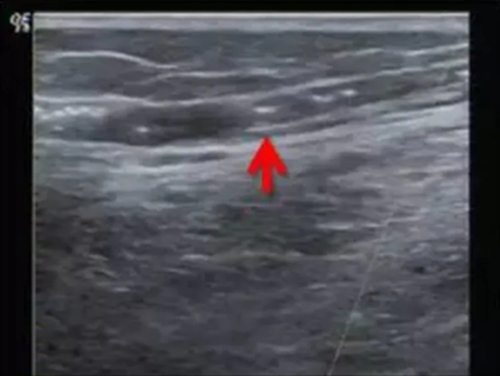

也可以在超聲引導(dǎo)下,更安全、可靠。

超聲看到硬化劑在血管內(nèi)彌散,血管即刻收縮!

精索靜脈曲張超聲引導(dǎo)硬化